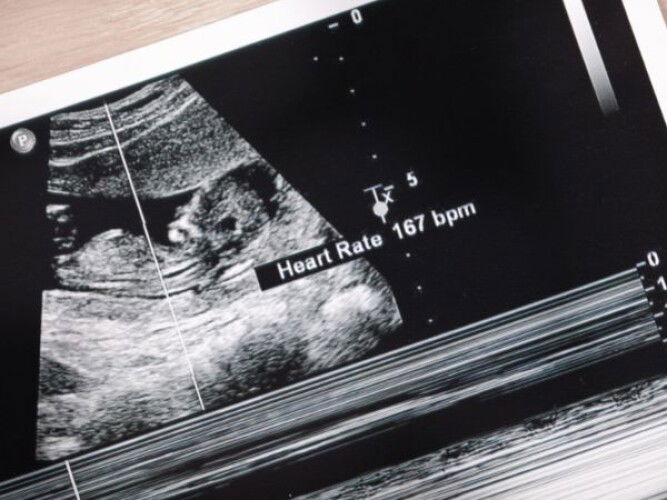

Did you hear your baby's' heart beat during first prenatal visit🧡?

Read about the first prenatal visit here: https://sg.theasianparent.com/first-prenatal-visit